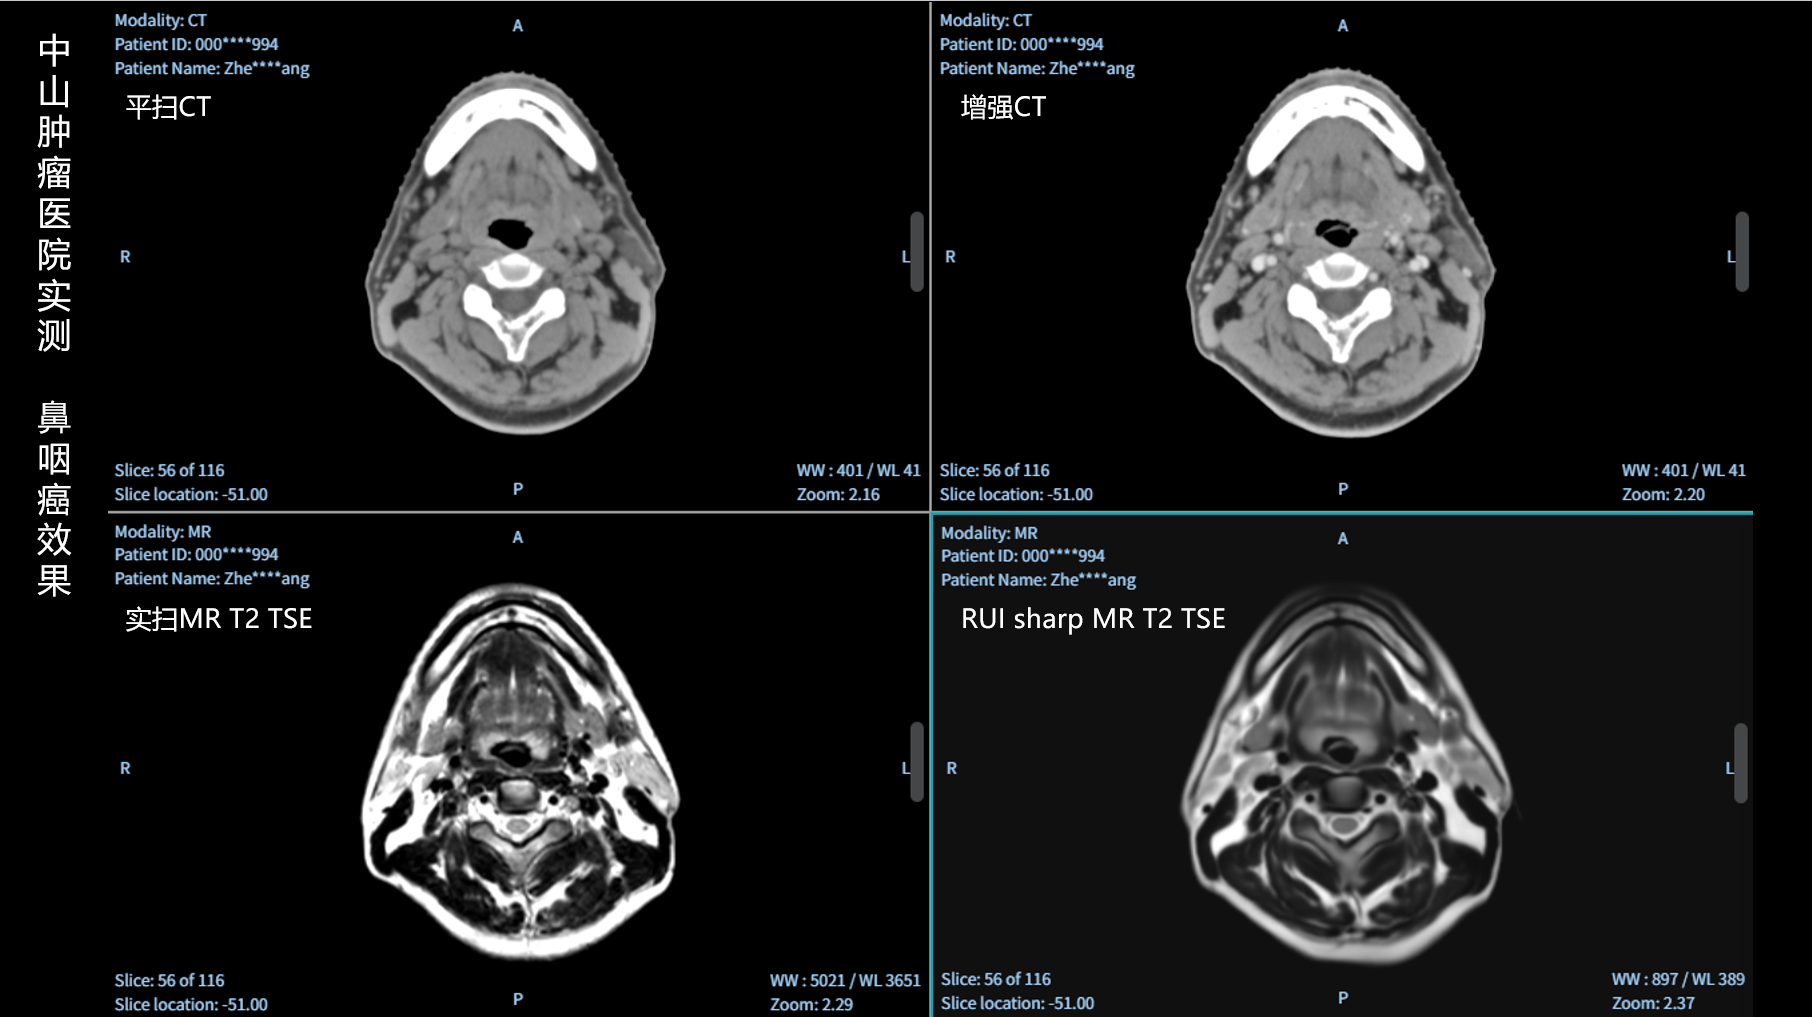

RUI sharp H(锐影)可在不依赖MRI的前提下,显著提升头部CT图像的软组织分辨率,为临床提供更高质量的辅助信息,尤其适用于MRI资源受限或较难配准的头颈部放疗感兴趣区勾画场景。

可大幅提高头部CT影像软组织分辨率,使肿瘤和周边器官显示更清晰,为放疗靶区勾画提供参考。

无需图像配准,CT和锐影图像同源,可匹配、叠加、"淡入淡出"显示。